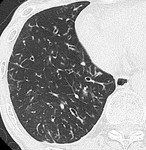

[画像診断]器質化肺炎のHRCT所見について 2010-09-21